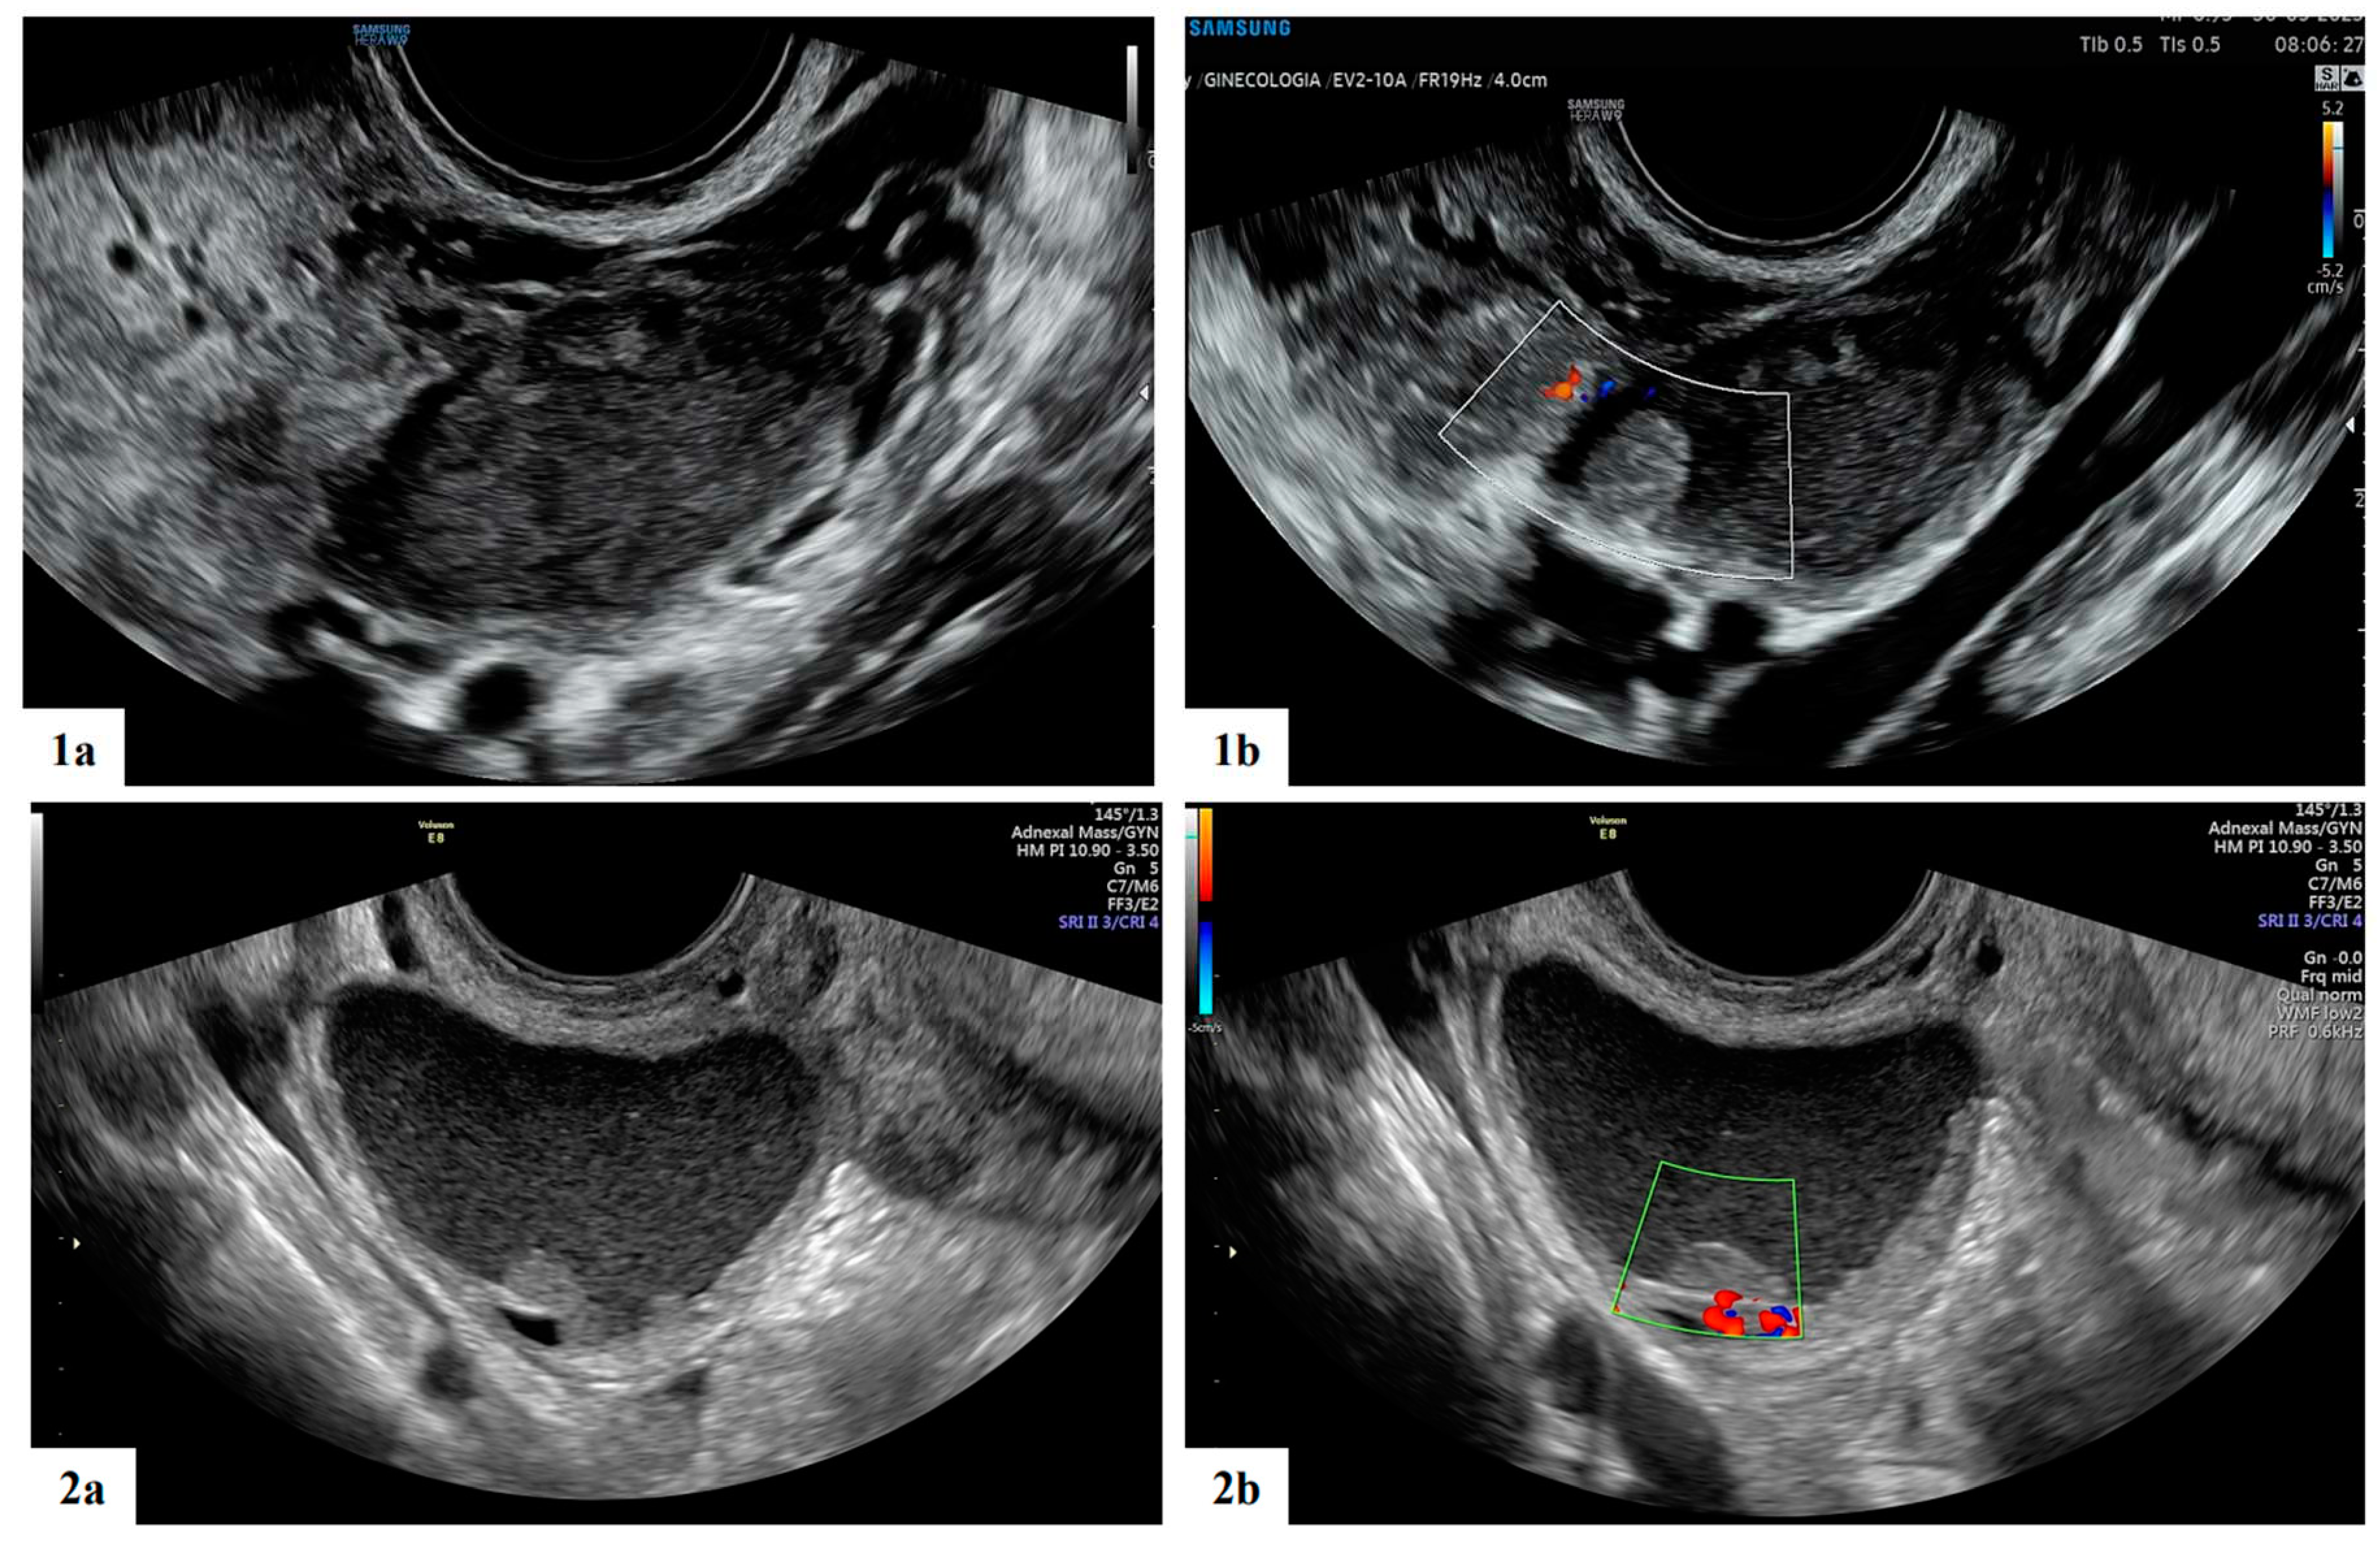

- Mascilini, F.; Moruzzi, C.; Giansiracusa, C.; Guastafierro, F.; Savelli, L.; De Meis, L.; Epstein, E.; Timor-Tritsch I., E.; Mailath-Pokorny, M.; Ercoli, A.; Exacoustos, C.; Benacerraf B., R.; Valentin, L.; Testa, A.C. Imaging in gynecological disease. 10: Clinical and ultrasound characteristics of decidualized endometriomas surgically removed during pregnancy. Ultrasound Obstet Gynecol 2014, 44, 354–360. [Google Scholar] [CrossRef]

| Presence of papillary projections | 4 |

| Number of papillary projections 1 2 3 |

1/4 2/4 1/4 |

| Papillation contour Irregular Smooth |

1/4 3/4 |

| Papillation flow Present Absent |

2/4 2/4 |

| Heigh of the largest papillary projection (mm) (range) | 7.5 (3-13) |

| Presence of crescent sign | 13 |